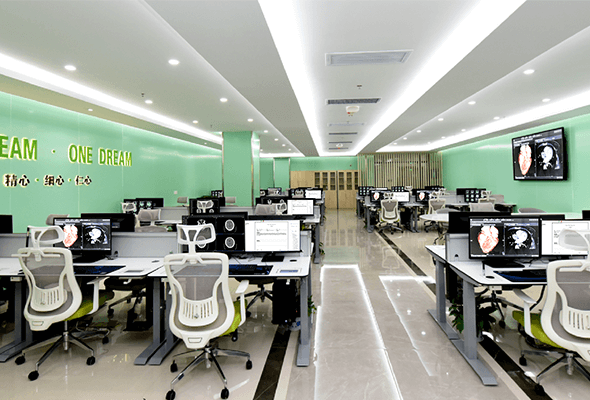

實和智能——I SEE HEALTH

作為國內專注于影像中心整體規劃設計、影像診斷軟硬件平臺配套研發生產的企業,實和擁有強大的研發能力,上海、長沙兩大產品研發中心,匹配了醫學工程、影像、軟件開發、交互設計領域的高精專研發團隊,涉及影像、生命傳感技術、AI等廣泛領域。

500+合作醫院和伙伴

2021年實和已完成500家公立醫院影像閱片中心,76家第三方影像中心的設計建設。